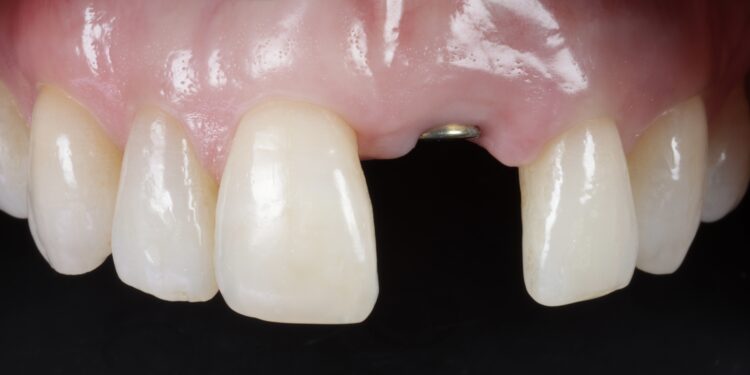

Once the orthodontic treatment was completed, the site was re-evaluated, and it was clear to see that the gingival zenith had significantly improved. The patient was advised that without re-contouring the mesial aspect of the contralateral central incisor there would be a midline black triangle. She rejected the option of composite addition to alter the triangular shape of the UR1 and thus we proceeded to complete the treatment without this. The implant was placed with simultaneous buccal GBR & connective tissue graft following a transmucosal approach. Following a healing period of 4 months, the restorative treatment was initiated with a temporary crown to develop the emergence profile. Once the gingival zeniths had been matched, the patient was delivered a permanent screw retained crown.